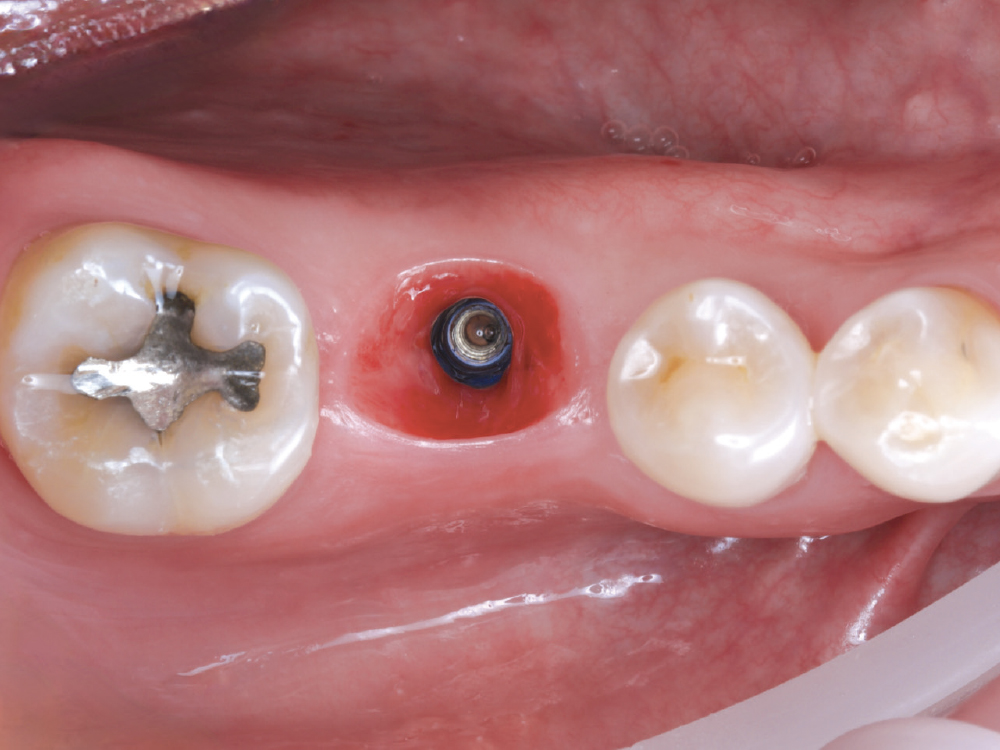

Capture the Surrounding Soft Tissue Immediately

Capture the Surrounding Soft Tissue Immediately. Scan the peri-implant soft-tissue architecture as soon as the scan body is placed, before the tissue collapse occurs. Gingival tissues begin to collapse and distort within minutes of scan body insertion, and the initial tissue contours are critical for creating proper emergence profiles. Work efficiently but thoroughly to document the tissue topography in its most accurate state.

Implant post scan on left side of mouth

Implant post scan pointing down

Implant post scan close up